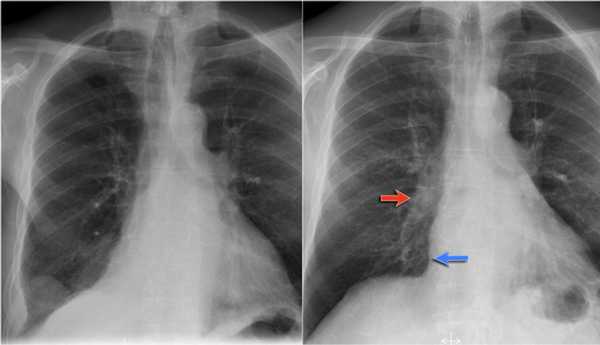

Ателектаз верхней доли правого легкого.

Оцените ниже лежащие изображения, а после продолжите чтение.

- Трехгранное затенение.

- Подъем правого корня легкого

- Облитерация загрудинного пространства (указано стрелкой).

На ПЭТ/КТ визуализируется опухоль легкого с обструкцией правого верхнедолевого бронха, как следствие ателектаз верхний доли правого легкого.

Также очень частым проявлением ателектаза является подъем диафрагмы, что хорошо визуализируется на ниже представленной рентгенограмме (указано синий стрелкой).

У данного пациента карцинома легкого с билатеральным метастазированием в легкие (указано красными стрелкам).